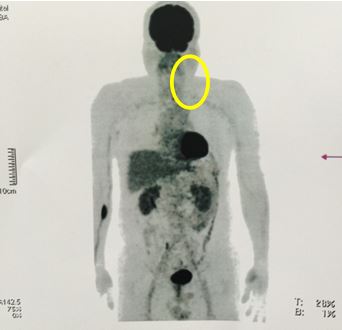

v Chụp PET/CT sau điều trị: khối hạch cổ trái tan biến hoàn toàn, không thấy tăng hấp thu FDG tại cơ quan bộ phận khác của cơ thể.

Hình 2: hình ảnh chụp PET/CT sau điều trị cho thấy khối hạch cổ trái tan biến hoàn toàn, không thấy tăng hấp thu FDG tại cơ quan bộ phận khác của cơ thể.

Hình 4: Trước điều trị: Hình ảnh khối hạch vùng cổ trái kích thước 10x12 cm, tăng hấp thu FDG mạnh (vòng tròn vàng).

Hình 5: Sau điều trị 4 tháng (6 chu kỳ hóa chất) : hình ảnh chụp PET/CT sau điều trị cho thấy khối hạch cổ trái tan biến hoàn toàn, không thấy tăng hấp thu FDG tại cơ quan bộ phận khác của cơ thể.